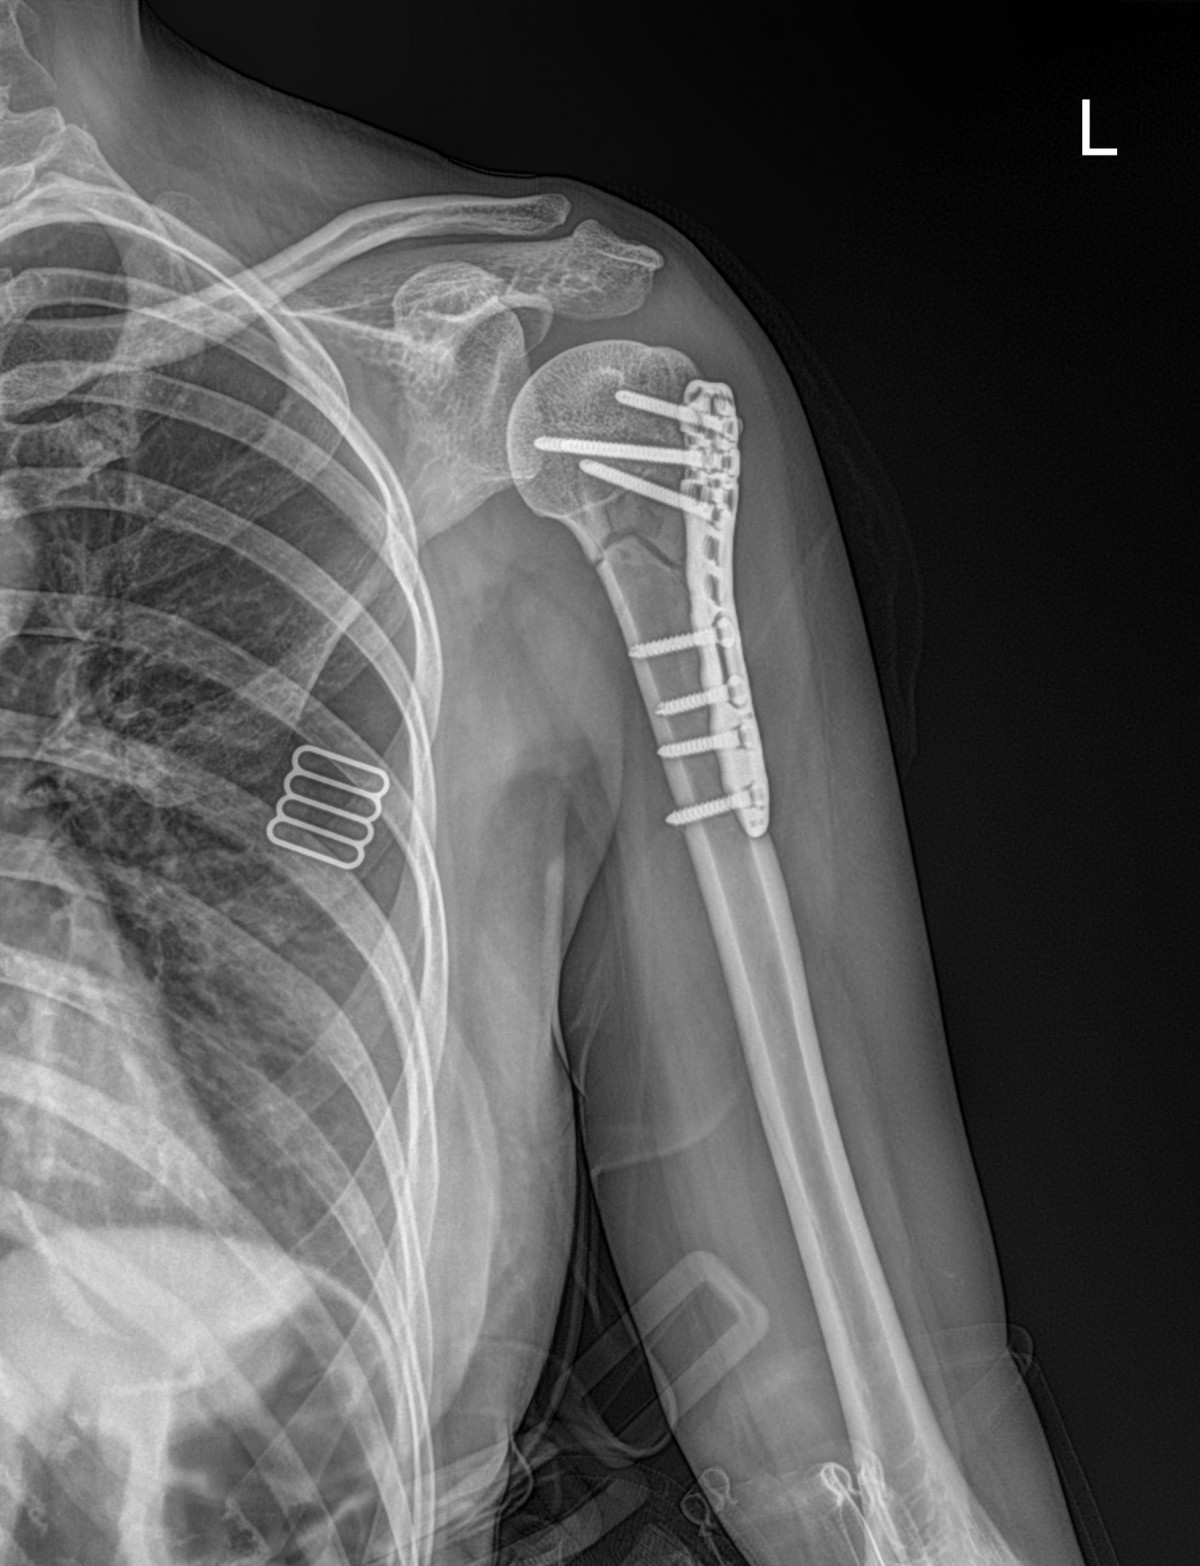

이재상원장님 어깨 골절 수술 구미O 환자

dae765e4d9ac96aee867c9d6292d8784_1758002764_4578.jpg